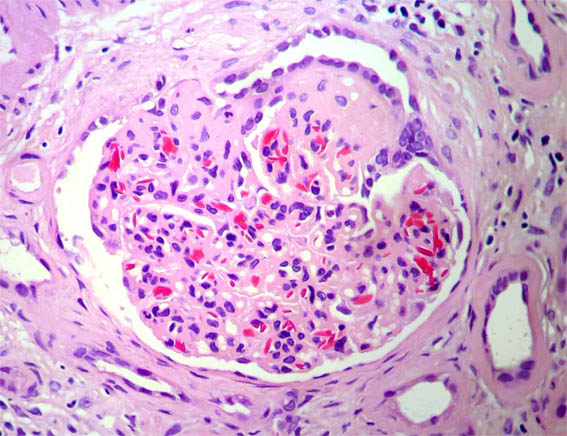

Figure 5.

H&E, X400.